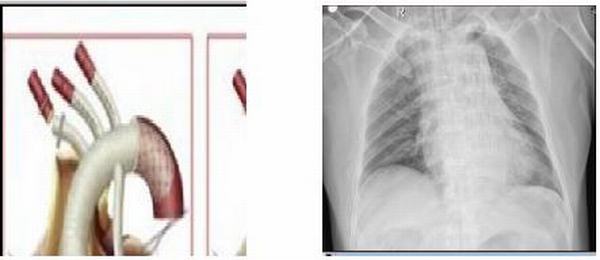

主動(dòng)脈夾層動(dòng)脈瘤四個(gè)預(yù)兆需警惕:

一、突發(fā)性劇烈的、撕裂樣的胸背部疼痛。臨床上,有90%的病人首發(fā)癥狀為突然發(fā)生的、持續(xù)性的、進(jìn)行性加重的劇烈胸痛,疼痛常在做某些突發(fā)動(dòng)作時(shí)出現(xiàn),如提重物、打籃球及異常激動(dòng)時(shí),甚至打哈欠、咳嗽、用力排便等動(dòng)作也可誘發(fā),由于呈刺痛、撕裂樣或刀割樣疼痛,患者往往不能忍受,此時(shí)大汗淋漓,有瀕死感,甚至因疼痛而昏厥。

二、胃腸道癥狀。若夾層波及主動(dòng)脈遠(yuǎn)端,即:腸系膜動(dòng)脈,患者可有腹痛、嘔吐、嘔血及便血等癥狀。

三、休克。大量出血,導(dǎo)致低血壓休克,心包填塞及大量胸腔積液,患者面色蒼白、大汗、精神緊張或暈厥,四肢末端濕冷,但血壓多能維持在高血壓范圍內(nèi)或略有下降。

四、精神神經(jīng)癥狀。若血腫累及頸動(dòng)脈或無名動(dòng)脈開口處,可表現(xiàn)為一過性腦缺血,甚至腦卒中。

主動(dòng)脈夾層是心血管系統(tǒng)急危重癥疾病,冬季更是高發(fā)季,它如一枚定時(shí)炸彈,臨床特點(diǎn)為急性起病,突發(fā)劇烈疼痛,休克和血壓迫主要的動(dòng)脈分支血管出現(xiàn)臟器缺血癥狀,如治療不及時(shí)發(fā)病48小時(shí)死亡率達(dá)50%。主動(dòng)脈夾層動(dòng)脈瘤主要的病因是高血壓。據(jù)統(tǒng)計(jì),80%~90%的夾層動(dòng)脈瘤患者合并有高血壓,且發(fā)病時(shí)一般已有10~15年的高血壓病史。主要是因?yàn)楦哐獕簳?huì)促進(jìn)中老年人的主動(dòng)脈退行性改變,從而降低動(dòng)脈壁各層組織間的黏合力,引起并加速夾層動(dòng)脈瘤的形成;所以控制好血壓顯得尤為重要,已經(jīng)確定診斷后,第一時(shí)間給予控制血壓、止痛對(duì)癥處理,血壓控制在有效灌注的情況下,維持在110-120mmHg/60-70mmHg較為理想。